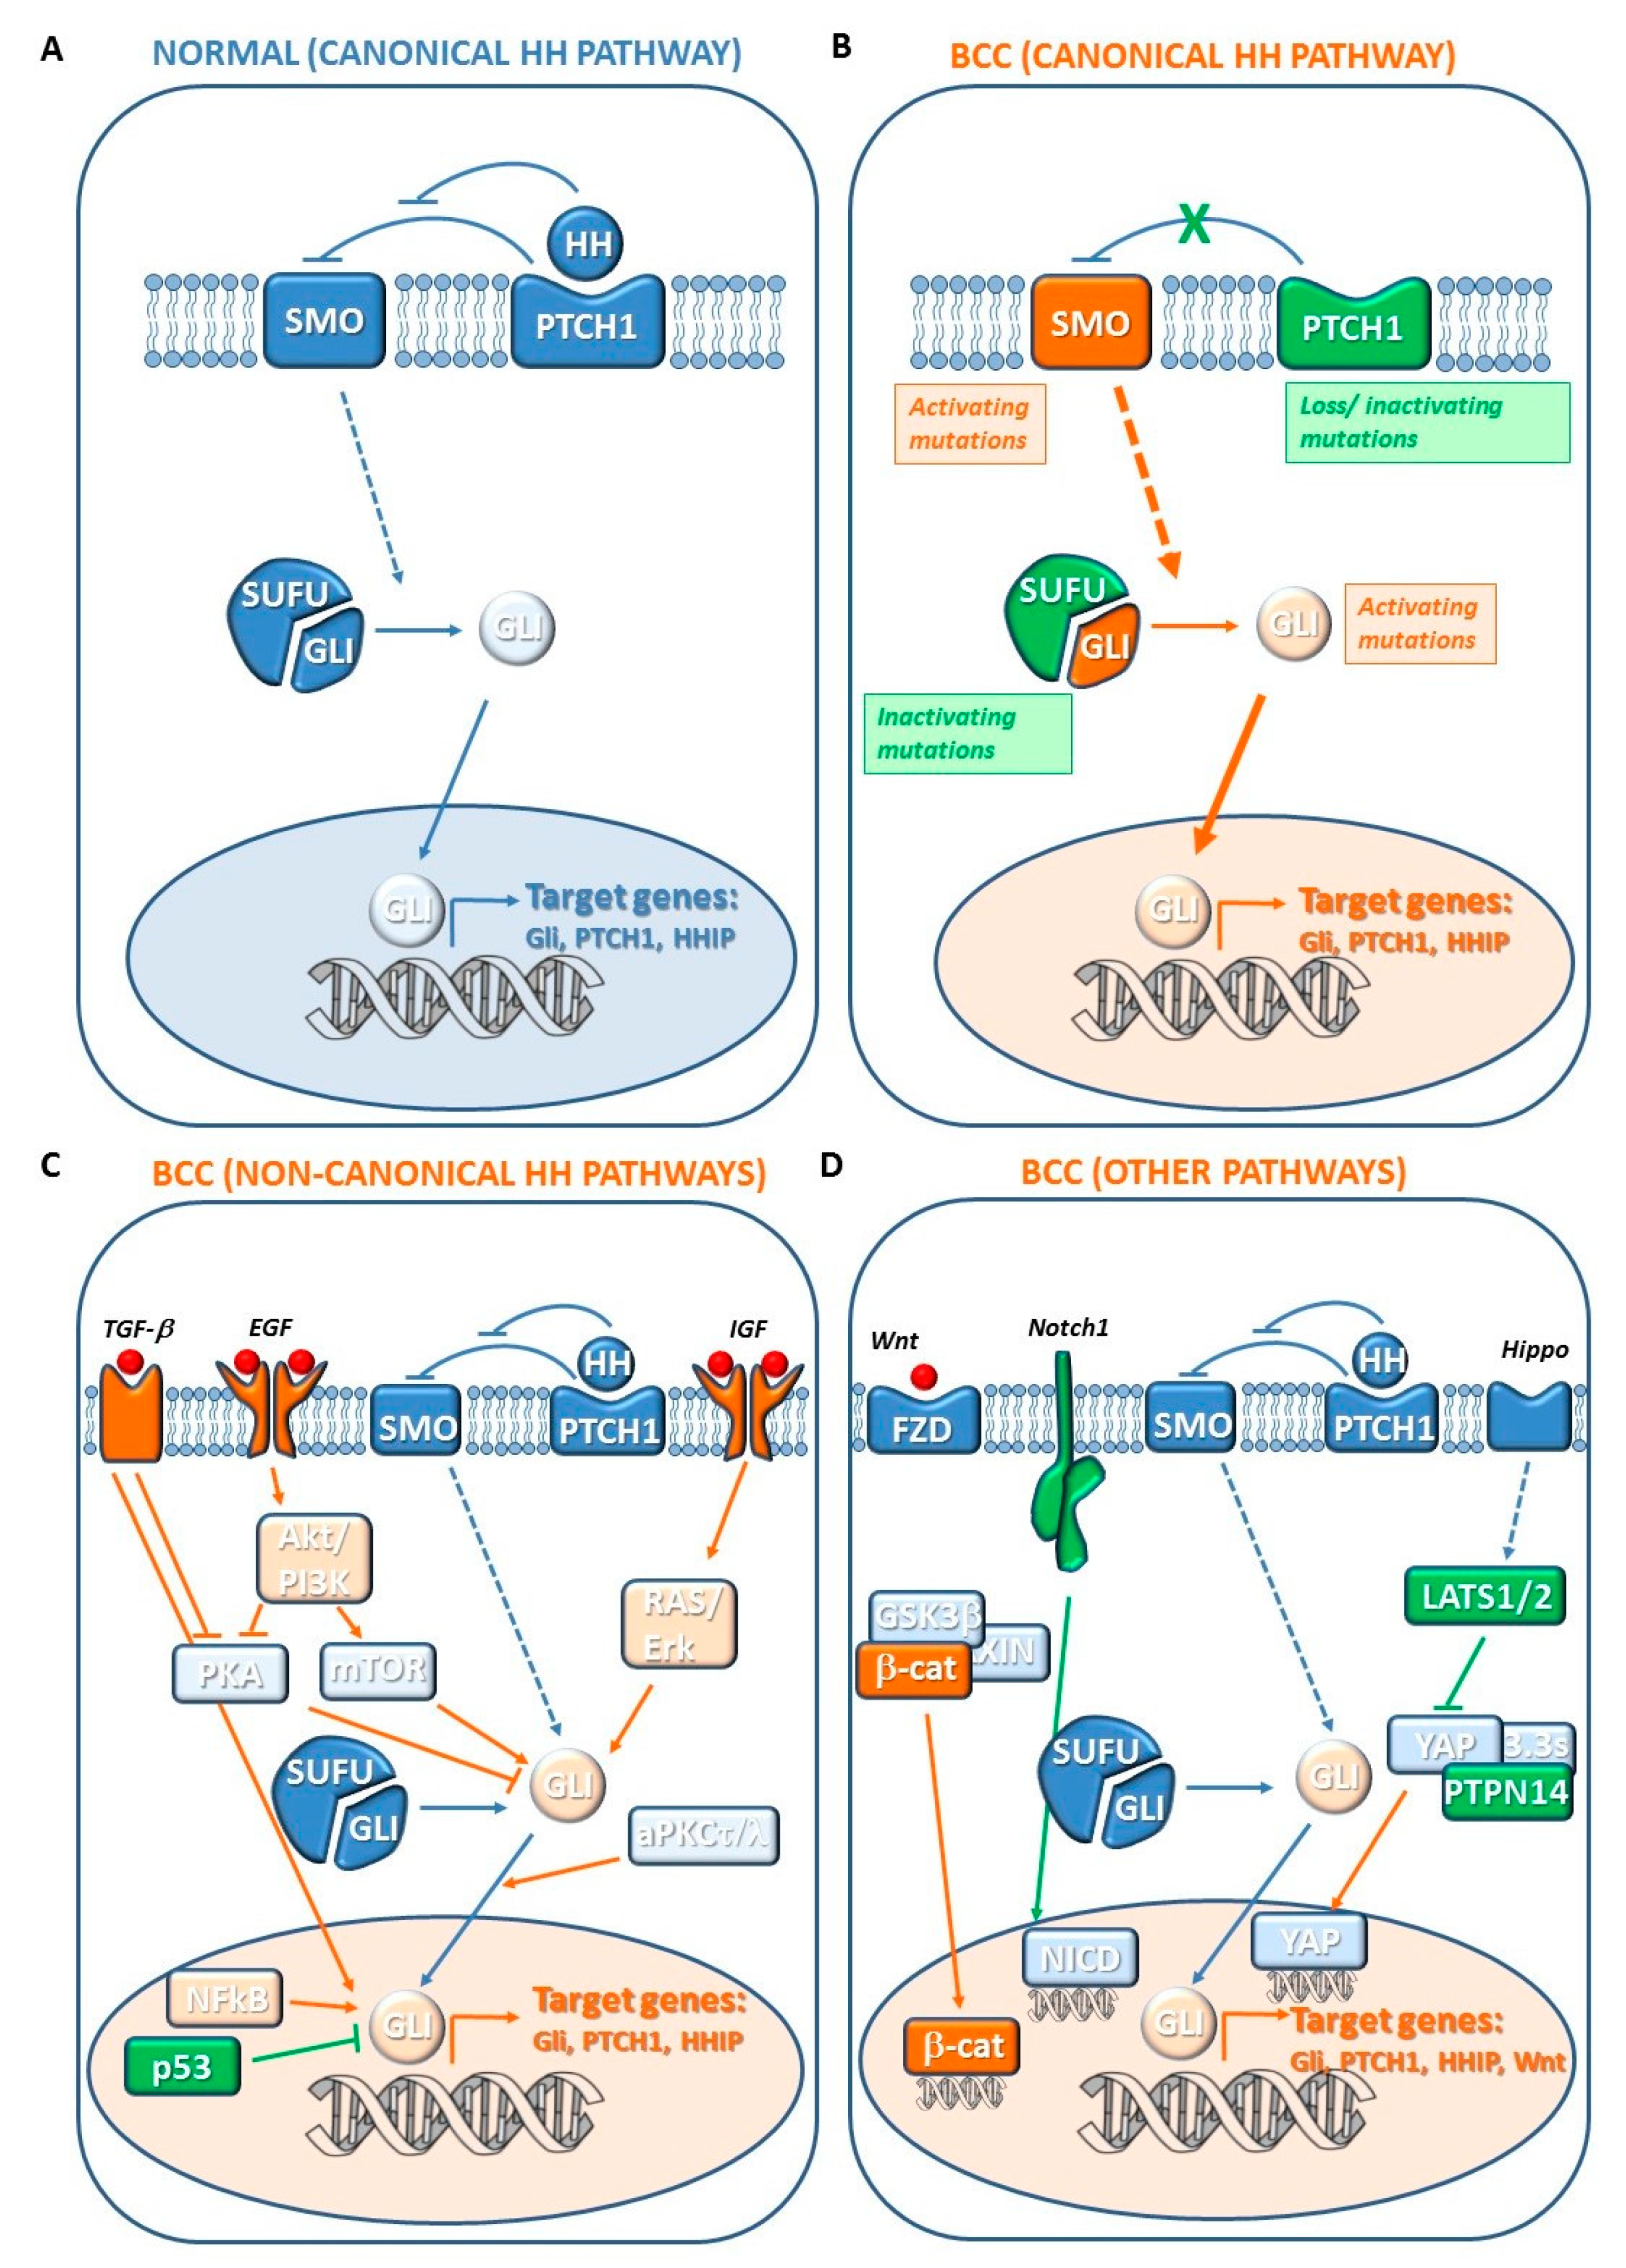

7. Pathogenesis of BCC

7.1. Canonical Hedgehog (HH) Pathway Genes

7.2. Noncanonical HH Pathway Genes

7.3. Other Genetic Changes

7.3.1. Hippo-YAP and WNT Signaling Genes